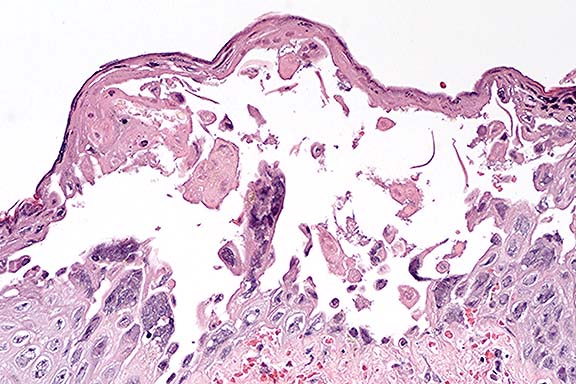

Case 27-1. Lip. The inner surface shows a vesicle containing necrotic acanthocytes and multincleated syncytial cells with diffuse, vague amphophilic nuclear inclusions. 20X

1. Dermatitis, vesicular, acute, multifocal with epithelial syncytial cells and eosinophilic intranuclear inclusions.

2. Subcuticular hemorrhage and vasculitis, multifocal (not present in all sections).

In contrast to the gross skin lesions, the microscopic lesions are relatively mild and include degeneration and necrosis of surface and adnexal epithelium and vesicle formation. Intranuclear viral inclusions are present in almost all affected epithelial foci. A mild variable neutrophilic infiltrate and multifocal subcuticular hemorrhage are present in the dermis of some affected sections. In sections with subcutaneous hemorrhage, small vessels are congested, lined by rounded endothelium and contain occasional fibrin aggregates. Some vessel walls are necrotic and rare endothelial cells contain intranuclear inclusions. Similar vascular lesions are present in the spleen.